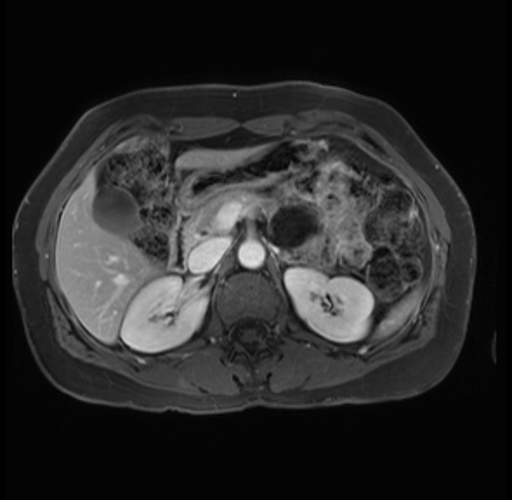

Imaging Analysis

Look through the patient's CT scan to identify any areas of concern for the necessary procedure.

Based on your CT findings, which issue(s) are present and would give reason for "planned slowing down moment(s)" in this case?

Considering a standard distal pancreatectomy procedure, what step(s) of the operation would you do differently in this case?